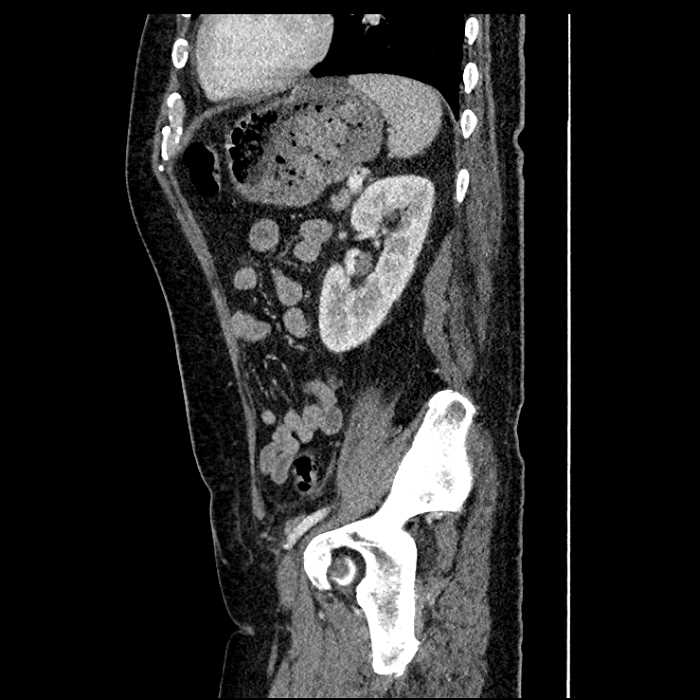

• Mild mural thickening of a segment of the sigmoid colon with adjacent fat stranding and a 1.5 cm fluid and gas collection along the tip of an inflamed diverticulum

• Loss of the normal fat plane between this collection and adjacent loops of small bowel, which demonstrate mural thickening

Acute sigmoid diverticulitis complicated by a small contained perforation and a large abscess in the right hepatic lobe. Additional small subcapsular abscesses along the anterior margin of the left hepatic lobe.

Additionally, loss of the normal fat plane between the peridiverticular collection and adjacent thickened loops of small bowel raises the potential for an enterocolonic fistula.

Hepatic abscess showing the double target sign with low density internally surrounded by a thin inner enhancing rim (red arrow) and ill-defined outer low density rim (yellow arrow). Blue arrow indicates an internal septation. Red arrows: additional smaller subcapsular abscesses. Red arrow: focal contained perforation associated with diverticulitis.